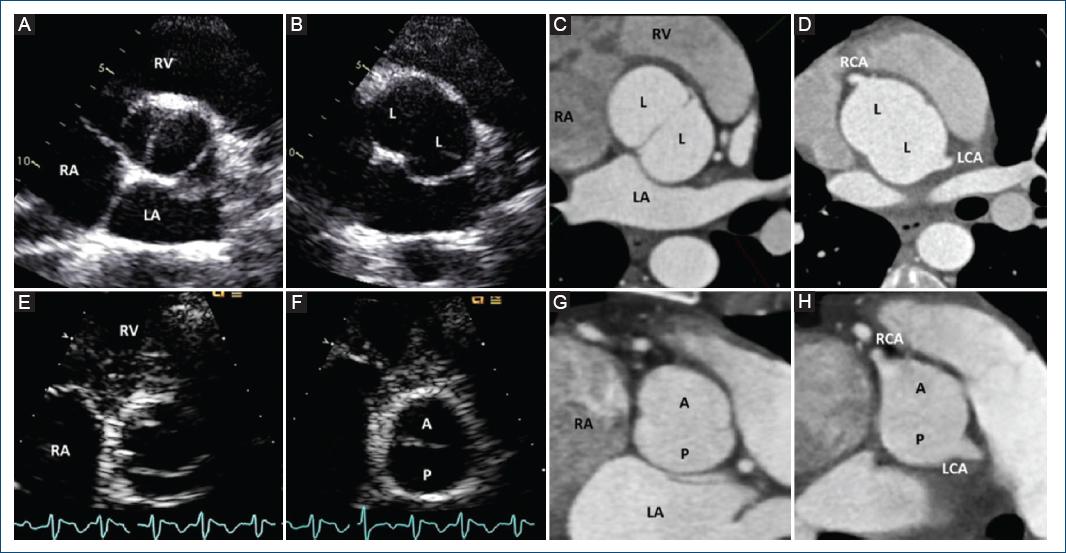

VÁLVULA AÓRTICA BICÚSPIDE DE DOS SENOS

La VAB de tipo dos senos es poco común, representando aproximadamente el 5-7% de los casos de VAB2,6,28. En contraste con el tipo fusionado, la apariencia de la VAB de dos senos no sugiere que dos de las tres cúspides se hayan fusionado, sino que hay dos cúspides de aproximadamente el mismo tamaño y forma, que cada una ocupa 180° de la circunferencia anular, y que estas se «formaron» dentro de dos senos aórticos solamente, lo que resultó en una válvula de dos senos/dos cúspides (Figs. 11 y 12) con ángulos comisurales de 180°. Es difícil determinar cuáles dos cúspides podrían haberse unido para formar una VAB de dos senos, pero generalmente es evidente si las cúspides son latero-laterales (de lado a lado) o antero-posteriores (adelante y atrás) dentro del plano de la base del corazón de eje corto (Figs. 11 y 12); por lo tanto, estos son los dos fenotipos específicos de la categoría de la VAB de dos senos. La VAB latero-lateral de dos senos tiene una arteria coronaria que surge de cada seno, mientras que la VAB antero-posterior puede tener una arteria coronaria que surge de cada seno o ambas arterias coronarias que surgen del seno anterior (Figs. 11 y 12). La VAB de dos senos probablemente representa una expresión más grave de los mecanismos embriológicos que conducen a la VAB fusionada. Es apropiado referirse a estos fenotipos como VAB latero-lateral de dos senos y VAB antero-posterior de dos senos. Ocasionalmente, a pesar de la sospecha, puede ser difícil estar seguro de si solo hay dos senos, en cuyo caso se pueden usar términos como posible o probable VAB de dos senos. Hay una falta de datos científicos sobre las asociaciones clínicas/pronósticas de la VAB de dos senos, que representa una forma «morfológicamente severa» de la VAB. Por lo tanto, esperamos que por medio de este sistema de nomenclatura/clasificación, la comunidad investigadora dirija más atención hacia este tipo de VAB.

Figura 11 Esquema de los fenotipos de la válvula aórtica bicúspide (VAB) de tipo dos senos vistos por el ecocardiograma transtorácico en eje corto paraesternal. Aplicable a vistas tomográficas similares obtenidas de la tomografía computarizada cardiaca y resonancia magnética cardiaca, la figura muestra fenotipos de VAB de dos senos como vistas ampliadas de la base del corazón para la correlación anatómica con los puntos de referencia. 1: VAB de tipo dos senos latero-lateral con solo dos senos aórticos distinguibles en diástole y dos cúspides de aproximadamente el mismo tamaño y forma, cada una ocupando 180° de la circunferencia, con un ángulo de 180° de las comisuras. Nótese que aunque es posible sospechar fusión derecha-no coronaria, las referencias anatómicas no están claras porque tanto las cúspides «izquierda» como «no coronaria» ocupan porciones de la ubicación anatómica normal de la cúspide «no coronaria», y la línea comisural posterior está casi alineada con el septum interauricular, dividiendo la ubicación anatómica de la cúspide no coronariana normal (Figs. 5 y 12). La VAB de tipo dos senos fenotipo latero-lateral tiene una arteria coronaria que surge de cada seno. 2A: una VAB de tipo dos senos fenotipo antero-posterior con solo dos senos aórticos distinguibles en diástole y dos cúspides de aproximadamente el mismo tamaño y forma, cada uno ocupando 180° de la circunferencia, con un ángulo de 180° de las comisuras. Nótese que aunque es posible sospechar fusión derecha-izquierda, las referencias anatómicas no están claras porque la línea comisural en realidad divide la ubicación anatómica normal de la cúspide izquierda, de modo que tanto la cúspide funcional anterior como la posterior parecen tener una «parte» de la cúspide izquierda normal (Figs. 5 y 12). 2B: una VAB de tipo dos senos fenotipo antero-posterior que se asemeja a una fusión derecha-izquierda fusionada pero sin rafé, con solo dos senos aórticos distinguibles en diástole y dos cúspides del mismo tamaño/forma, cada uno ocupando 180° de la circunferencia. La VAB antero-posterior de dos senos puede tener arterias coronarias que surgen de cada cúspide (2A) o desde la cúspide funcional anterior (2B) (modificada de Michelena et al., 20206 con permiso de Elsevier).

Figura 12 Imágenes diastólicas y sistólicas de eje corto de los fenotipos de la válvula aórtica bicúspide de dos senos obtenidas a partir de ecocardiografía transtorácica y diastólicas de tomografía computarizada cardiaca con sincronización electrocardiográfica. A: una válvula aórtica bicúspide de dos senos latero-lateral en sístole, con la línea comisural dividiendo la posición anatómica normal de la cúspide no coronaria (B-C), con solo dos senos aórticos distinguibles en diástole (B), y cúspides de tamaño/forma aproximadamente iguales que ocupan 180° de la circunferencia, reproducibles en un corte de tomografía equivalente como se ve con la tomografía computarizada cardiaca (C). Observe las arterias coronarias que surgen una de cada cúspide (D). E: una VAB de dos senos antero-posterior en sístole, con la línea comisural dividiendo la posición anatómica normal de la cúspide coronaria izquierda. F: imagen diastólica con solo dos senos aórticos distinguibles y cúspides de tamaño/forma aproximadamente iguales que ocupan 180° de la circunferencia, reproducibles en un corte tomográfico equivalente como se ve con la tomografía computarizada cardiaca (G). Observe las arterias coronarias que surgen una de cada cúspide en este ejemplo en particular (H). RA: aurícula derecha; RV: ventrículo derecho; LA: aurícula izquierda; A: cúspide anterior; P: cúspide posterior; L: cúspide lateral; RCA: arteria coronaria derecha; LCA: arteria coronaria izquierda.